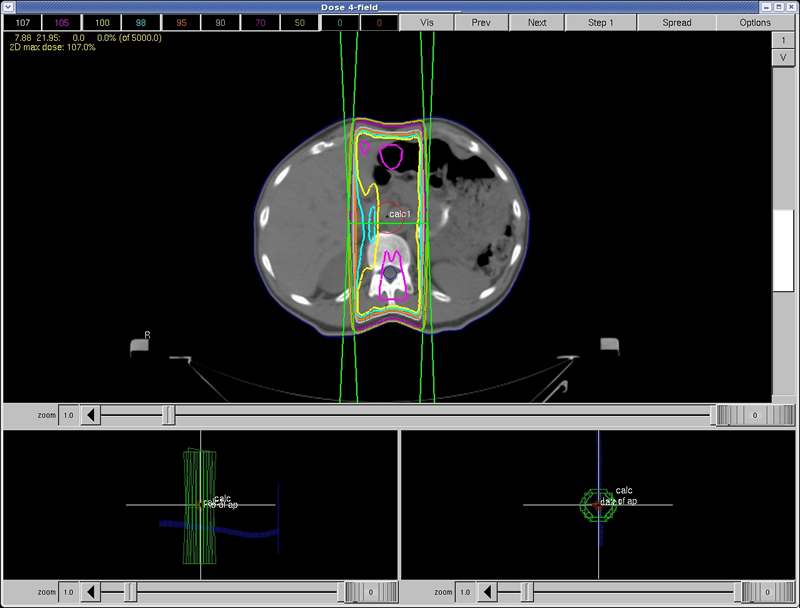

In this treatment plan, the dose to the spinal cord is approximately:

a) 25% of the total dose b) 50% of the total dose c) 75% of the total dose d) 105% of the total dose